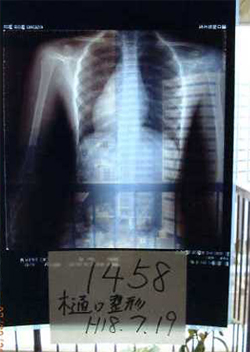

症例6)

初診18〜20度体操6ヶ月後ほぼ真っ直ぐと診断。

小学4年生10歳 学校検診で発見

●当時のレントゲン

●送られてきた葉書

2005年8月22日

2006年12月12日

20度くらい

プライバシーのため氏名は伏せてあります。

考察

体操はあきらめないでして頂くことが大事であり、母と子の努力の好結果です。

現在の病院では、なにも治療法がないといいますが、症例(4)(5)(6)のごとく低度数でも大塚式鍛錬体操の継続で改善が見られることが

多くのレントゲンで証明されています。